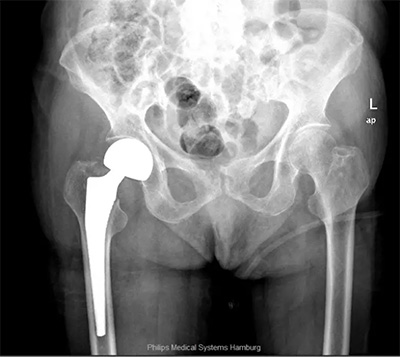

1、老年股骨頸骨折髖關(guān)節(jié)置換

對(duì)于老年股骨頸骨折或者部分粗隆間骨折,髖關(guān)節(jié)置換具有其獨(dú)特的優(yōu)勢(shì),科室將髖關(guān)節(jié)置換結(jié)合快速康復(fù)理念的應(yīng)用,在臨床上并取得了明顯的效果——有效的預(yù)防深靜脈血栓的形成,減少了臥床并發(fā)癥的發(fā)生,早期下地步行活動(dòng),明顯提高了老年術(shù)后患者的生活質(zhì)量。

2、髖關(guān)節(jié)翻修術(shù)

人工髖關(guān)節(jié)的平均壽命在15至20年左右,有于假體使用時(shí)間的延長(zhǎng),假體的磨損,將會(huì)出現(xiàn)關(guān)節(jié)松動(dòng)、下沉、磨損及假體周圍骨溶解等問(wèn)題,從而導(dǎo)致患者關(guān)節(jié)再次出現(xiàn)疼痛。如果人工關(guān)節(jié)松動(dòng)、脫位、髖臼磨損等問(wèn)題導(dǎo)致關(guān)節(jié)疼痛影響生活,可以通過(guò)人工髖關(guān)節(jié)翻修手術(shù)解決病人痛苦,提高生活質(zhì)量。